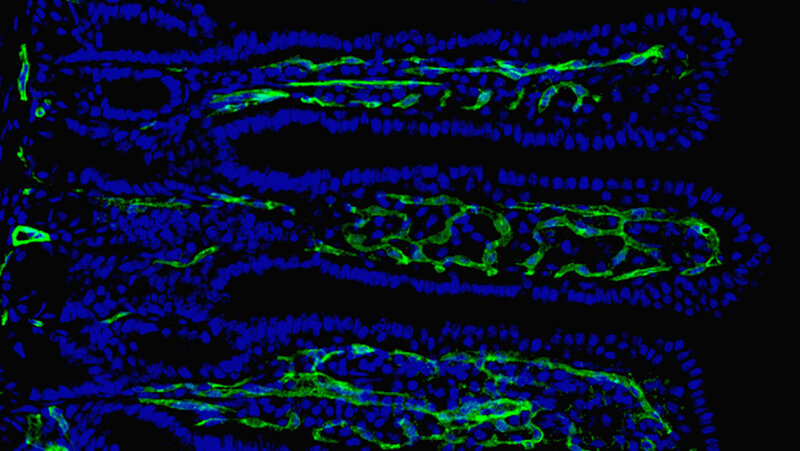

Forschende am CTH der Universitätsmedizin Mainz haben gezeigt, dass Darmbakterien die Darmbarriere schwächen und dadurch die Entstehung von Darmerkrankungen beeinflussen können. Das Bild zeigt eine mikroskopische Aufnahme von Dünndarmzotten mit Kapillargefäßen (grün) und Zellkernen (blau). © Universitätsmedizin Mainz / Christoph Reinhardt

Darüber hinaus entdeckte das Forschungsteam, dass ein Mangel an Neuropilin-1 die Bildung von Gefäßen in den Darmzotten beeinträchtigt. Diese Kapillargefäße sind besonders wichtig, um Nährstoffe effektiv aufnehmen zu können.